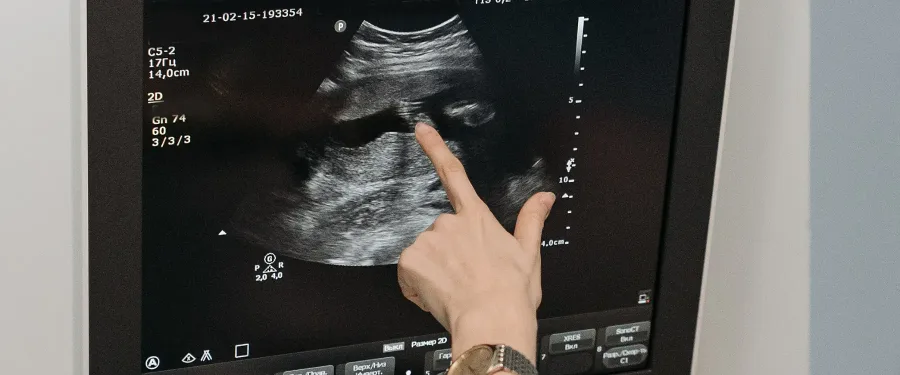

There are majorly 2 methods to determine your ovarian reserve. First is undertaking the Transvaginal Ultrasound/ TVS done at the second day of your menses. By this the doctor can make a check of the number of small follicles that are also called as antral follicles in both your ovaries. It is called AFC (ANTRAL FOLLICLE COUNT).